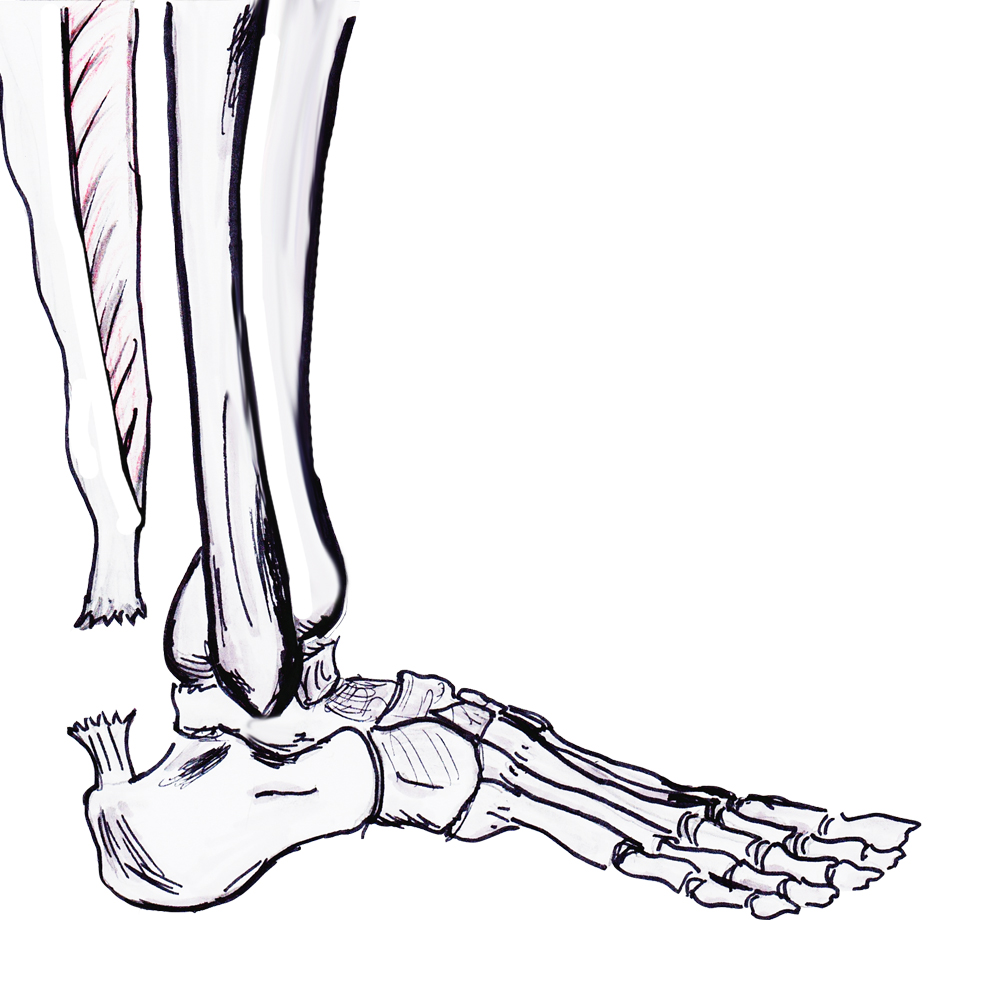

Rupture Site

1. Watershed area

- 5 - 7 cm proximal to insertion

- most common

2. Insertion - insertional tendonitis / diabetes / obestiy

3. Musculotendinous juntion

- avulsion of medial or lateral head

- may present with chronic weakness